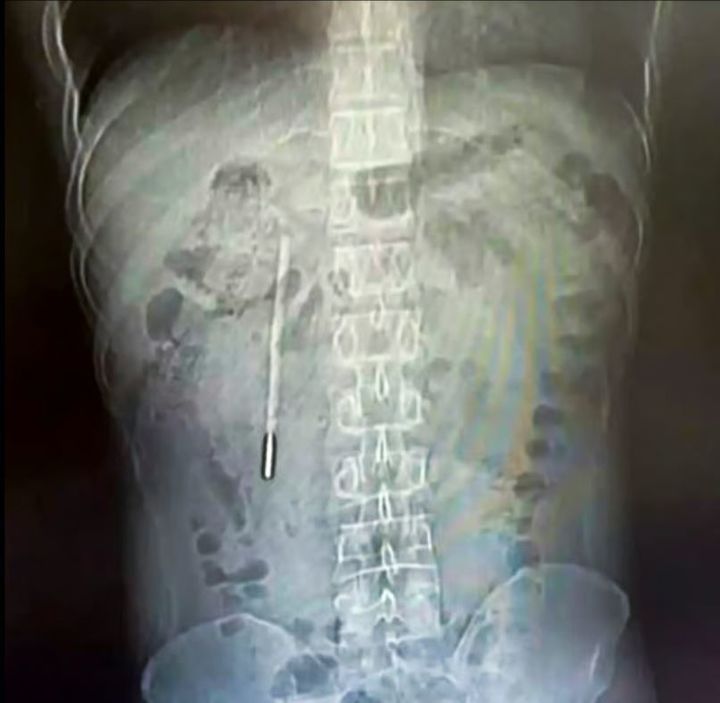

[서울=뉴시스] 왕씨의 몸속에 들어간 수은 체온계를 보여주는 엑스레이 이미지다. (사진=웨이보)

정밀 검사 결과 해당 물체는 어린 시절 삼킨 수은 체온계로 확인됐다. 체온계는 십이지장 부위에 걸린 채 장기간 머물러 있었으며 끝부분이 장벽에 닿아 천공이나 내부 출혈로 이어질 수 있는 위험한 상태였던 것으로 전해졌다.

의료진은 내시경을 통해 약 20분 만에 체온계를 제거했다. 체온계는 오랜 기간 담관 인근에 위치해 있었지만 파손되지는 않았으며 수은 유출도 발생하지 않았다. 다만 외부 눈금은 대부분 흐려진 상태였다.